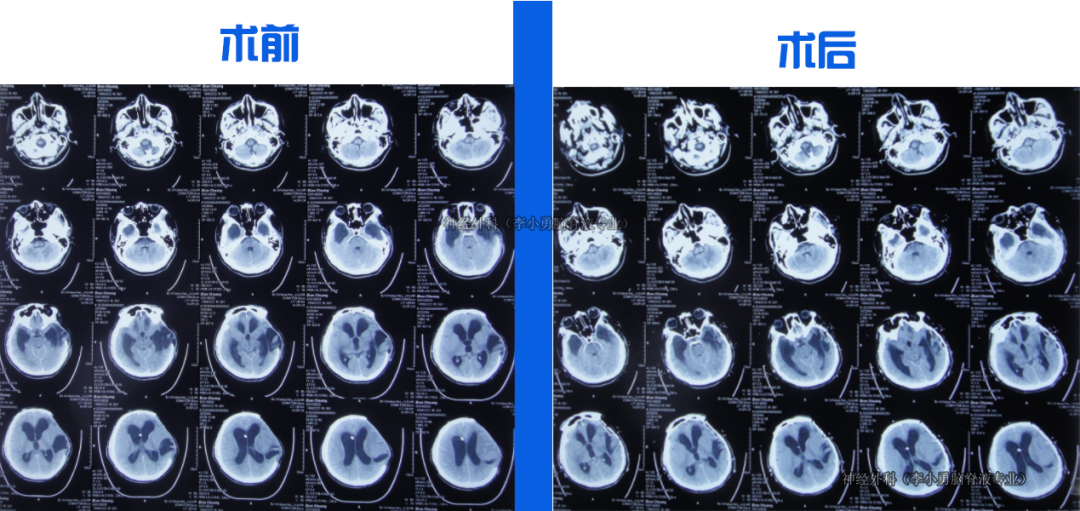

入院時:意識模糊,右上肢活動差,鼻飼、留置尿管。CT示顱骨缺損、腦積水、腦膨出。

入院當天行腦室外引流術。治療18天后意識轉清,腦脊液由渾濁變清亮。第22天改為腦室腹壁外引流,持續(xù)引流、抗感染、控制顱內(nèi)壓力。第36天骨窗開始塌陷,提示顱內(nèi)壓力有效控制。住院1月零23天行顱骨修補術。